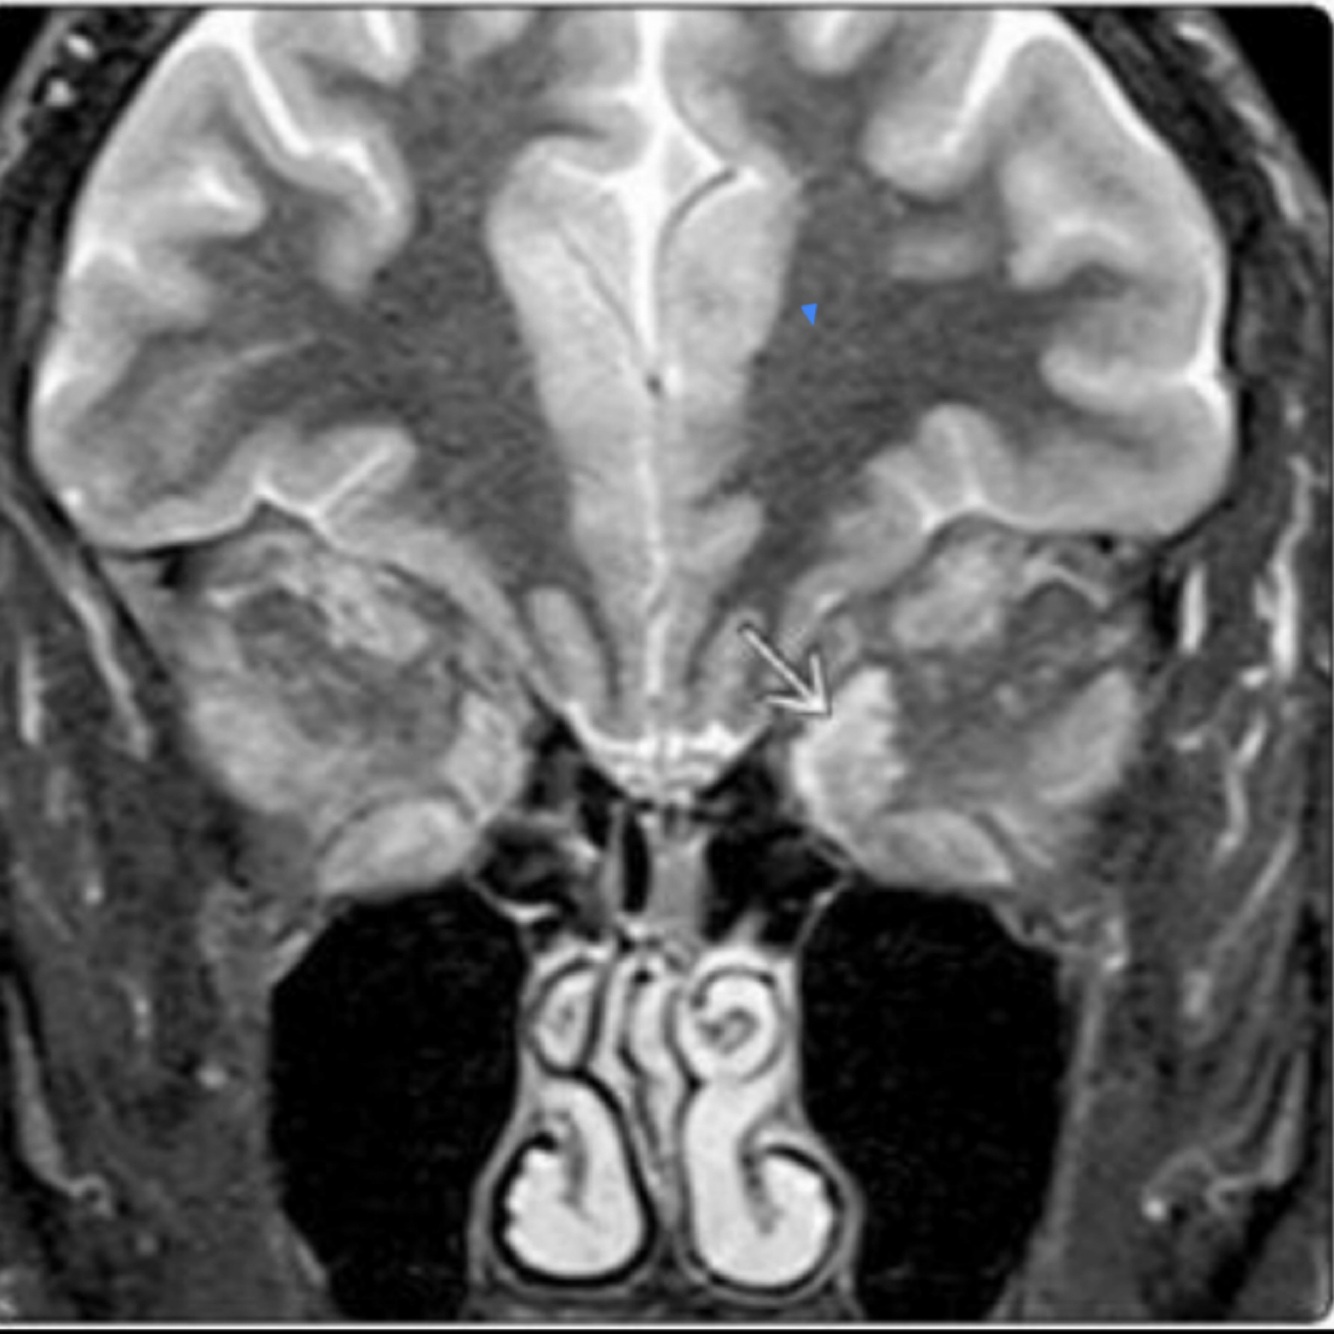

14

Q

Hallazgos en RM:

A

• Evaluar implicaciones intra y extraoculares

• Hemorragia

• Mejor caracterización de lesión en pineal

How well did you know this?